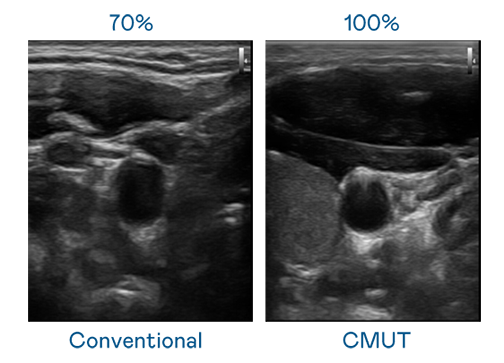

CMUT 技术是一种用电容式微机电元件来产生超音波讯号的技术。与传统 PZT 压电式技术相比,CMUT 频宽增加 30%,更宽频的超音波讯号让影像解析度大幅提升,是实现高影像品质医疗超音波扫描、促进精准医疗发展的关键技术。

大频宽带来超清晰影像

超音波影像的解析度高低,首先取决于探头能发出的讯号频宽。BG大游 CMUT 可提供高清晰的超音波讯号,提供高频宽、高灵敏度、影像纹理细节更高的超音波影像,协助医护人员缩短影像判读时间及利用精准的医疗影像进行诊断。